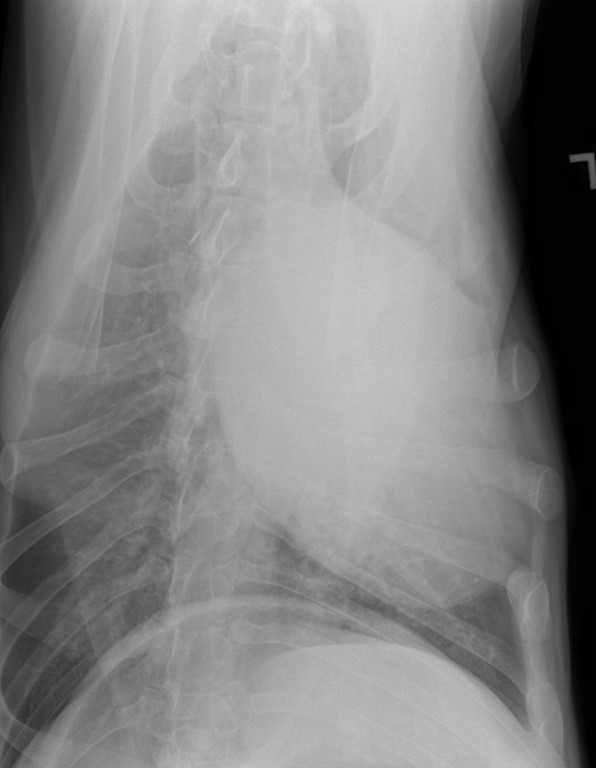

The Vet and I discussed x-days of her chest/lungs for her Vet was not comfortable with the looks of that remaining mass. frown emoticon Nor, with this sudden huge weight loss.

I was so worried gowning up to help with the x-Rays……

The good news is that her lungs, at this time have shown no signs of anything that has metastisized.

I have her x-Rays to post on her blog, photo’s of her masses and, one of a recovering sweet BHRR’s Ani from sedation. She also received a lovely mani/pedi!